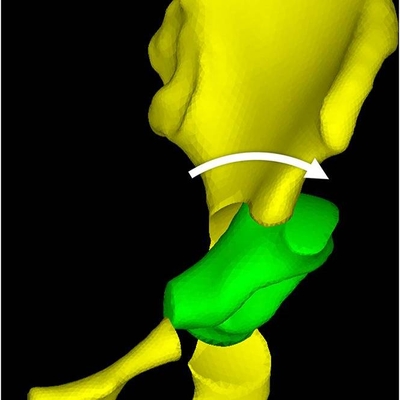

Click on an image below to view more info.